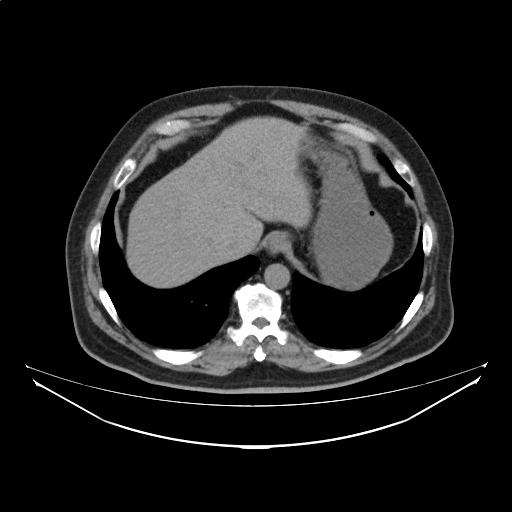

CTスライス1

(Findings)

肺野に明らかな活動性炎症像および腫瘤性病変を認めない。

縦隔、肺門、鎖骨上窩にリンパ節の病的腫大なし。

胸水を認めない。

胃に明らかな病的壁肥厚は指摘できないが、消化管病変の評価については内視鏡検査が望まれる。

軽度脂肪肝を認める。肝内に明らかな占拠性病変(SOL)を認めない。

胆嚢、膵、腎、脾、副腎に特記すべき異常所見を認めない。

傍大動脈領域にリンパ節の病的腫大を認めない。

腹水を認めない。

(Impression)

撮像範囲内に特記すべき異常所見を認めない。